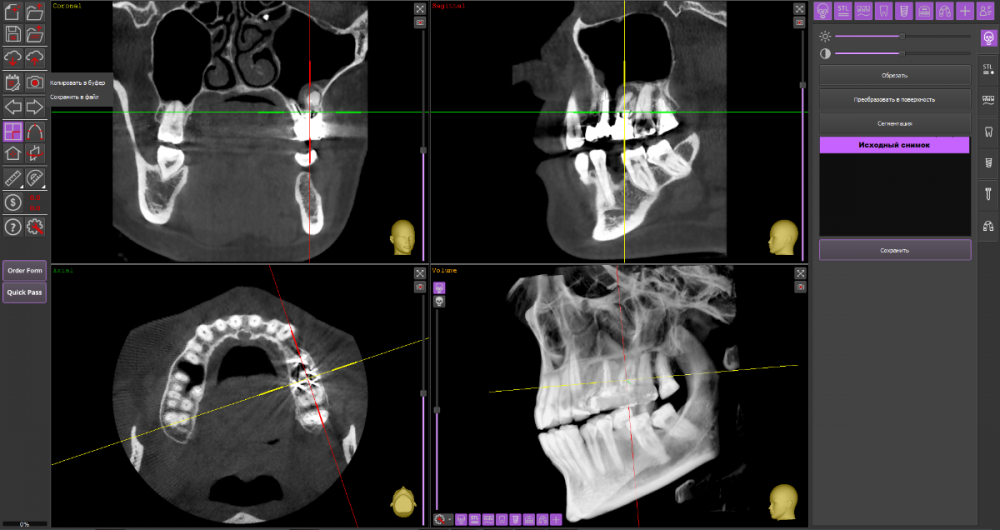

DeLaMer Опубликовано 11 августа, 2021 Поделиться Опубликовано 11 августа, 2021 (изменено) Добрый день уважаемым докторам-участникам форума. Хотелось бы, по возможности, получить экспертное мнение по поводу моей проблемы. На верхней челюсти есть мост, объединяющий 6й, 5й и отсутствующий 4 зубы (если я правильно понимаю нумерацию, это должны быть 24, 25, 26). В начале июня на десне открылся свищ с гноем (абсцесс, но, видимо, не острый, кроме периодического надувания гнойного шарика ничего больше не происходило). По этом поводу мой лечащий врач поднял КТ, которое было сделано осенью до того по другому поводу и обнаружила воспаление одного из корней 6-го зуба. При этом она высказала соображение, что может быть здесь поможет резекция верхушки того самого корня. Один из хирургов, с которым я консультировалась по этому поводу, сказал, что на его взгляд резекция возможна. Другой - что воспаление проявляется не только на одном корне, а на двух и по его мнению сделать тут ничего нельзя, только распиливать коронку и удалять 6й зуб. Я была бы крайне благодарна, если бы уважаемые специалисты высказали свое мнение по этому поводу, потому что при равноценных двух противоположных мнениях мне даже не понятно с чего начинать. Прикрепляю ссылку на файл КТ на своем дропбоксе. Огромное спасибо за помощь https://www.dropbox.com/s/fkv8cvqqq6grgpe/Sergeeva A..zip?dl=0 Изменено 11 августа, 2021 пользователем DeLaMer Ссылка на комментарий

Irouil Опубликовано 12 августа, 2021 Поделиться Опубликовано 12 августа, 2021 По представленным средам создаётся впечатление, что у зуба фактически разрушено соединение между корнями. Риски того, что он под нагрузкой раскроется в любой момент, достаточно высоки Ссылка на комментарий

АнтонТЛТ Опубликовано 13 августа, 2021 Поделиться Опубликовано 13 августа, 2021 (изменено) Там всё ок с фуркацией и вкладка коротконогая. Просто на КТ очень много артефактов. Изменено 13 августа, 2021 пользователем АнтонТЛТ Ссылка на комментарий